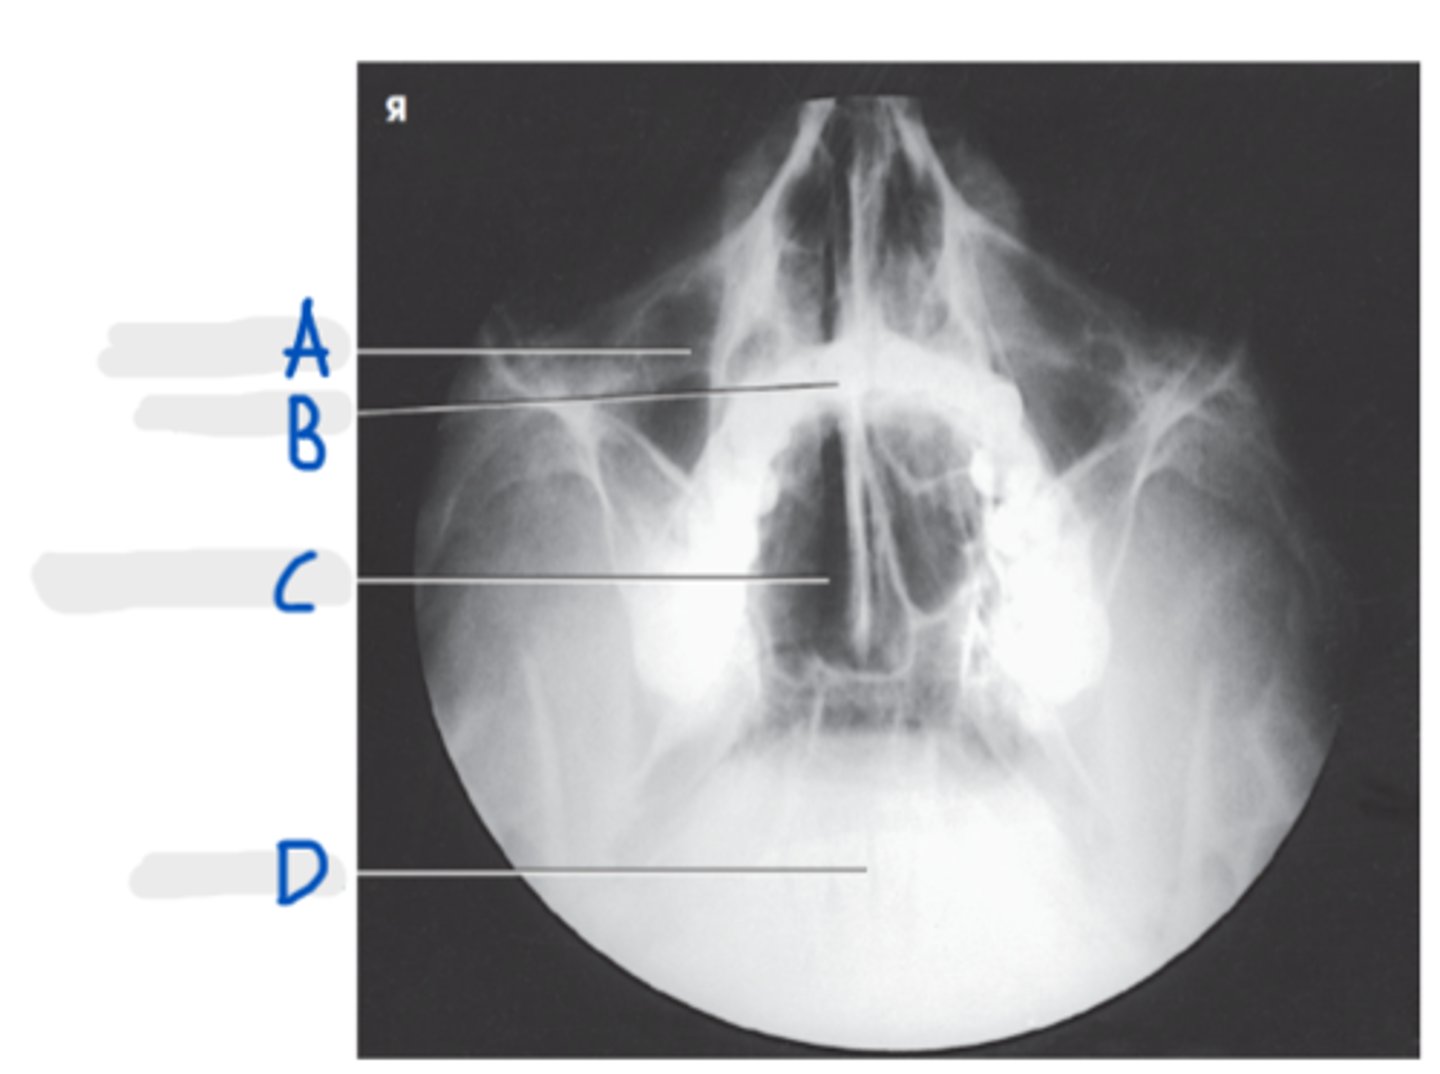

Maxillary sinus

A

Upper teeth

B

Sphenoid sinuses

C

Lower teeth

D

Parietoacanthial transoral (Open-Mouth Waters Method)

What is the specialty projection for sinuses?

Parietoacanthial Transoral (Open-Mouth Waters)

What projection is this?

Lips-meatal line (LML)

What line is perpendicular to the IR for PA Transoral (Open-Mouth Waters)?

CR exit at acanthion

What is the CR for a PA Transoral (Open-Mouth Waters)?